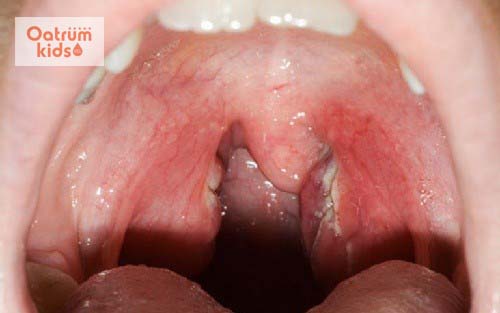

Viêm amidan hốc mủ

Viêm amidan hốc mủ là tình trạng nhiễm trùng do sự tấn công của virus, vi khuẩn. Những sinh vật này sinh sống quá nhiều trên bề mặt amidan sẽ khiến tổ chức này bị viêm. Khi amidan bắt đầu chống lại sự viêm nhiễm sẽ tiết ra cục mủ trắng như bã đậu. Khi dùng tay ấn vào có thể khiến mủ chảy ra, ho có đờm lẫn mủ trắng,... Bệnh này là hậu quả của bệnh viêm amidan cấp không được điều trị triệt để. Chính vì thế đây là một bệnh mãn tính và việc điều trị trở nên khá khó khăn.